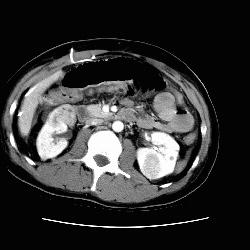

RADIOLOGY: KIDNEY: Case# 33026: TS, MULTIPLE RENAL TUMORS, ?AML. 26 year old male. 1) Large right pleural effusion and adjacent atelectasis. 2) Ascites with peritoneal enhancement may represent peritonitis. VP shunt catheter tubing coiled in the right upper quadrant. 3) Multiple enhancing heterogeneous renal lesions bilaterally. This is a appearance possible for angiomyolipomas although not diagnostic. Lower right renal lesion appears to be an angiomyolipoma. Renal cell carcinoma is also a possibility.